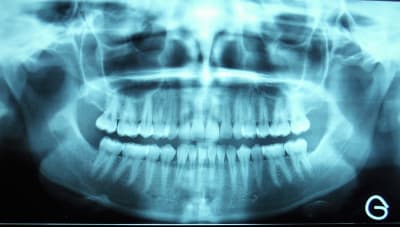

sans commentaire.

Ah si! 64 ans... et 41, 31 HS...

Lui 59 ans, 41 HS, c'est la semaine!!! les photos ne sont pas tops :-(